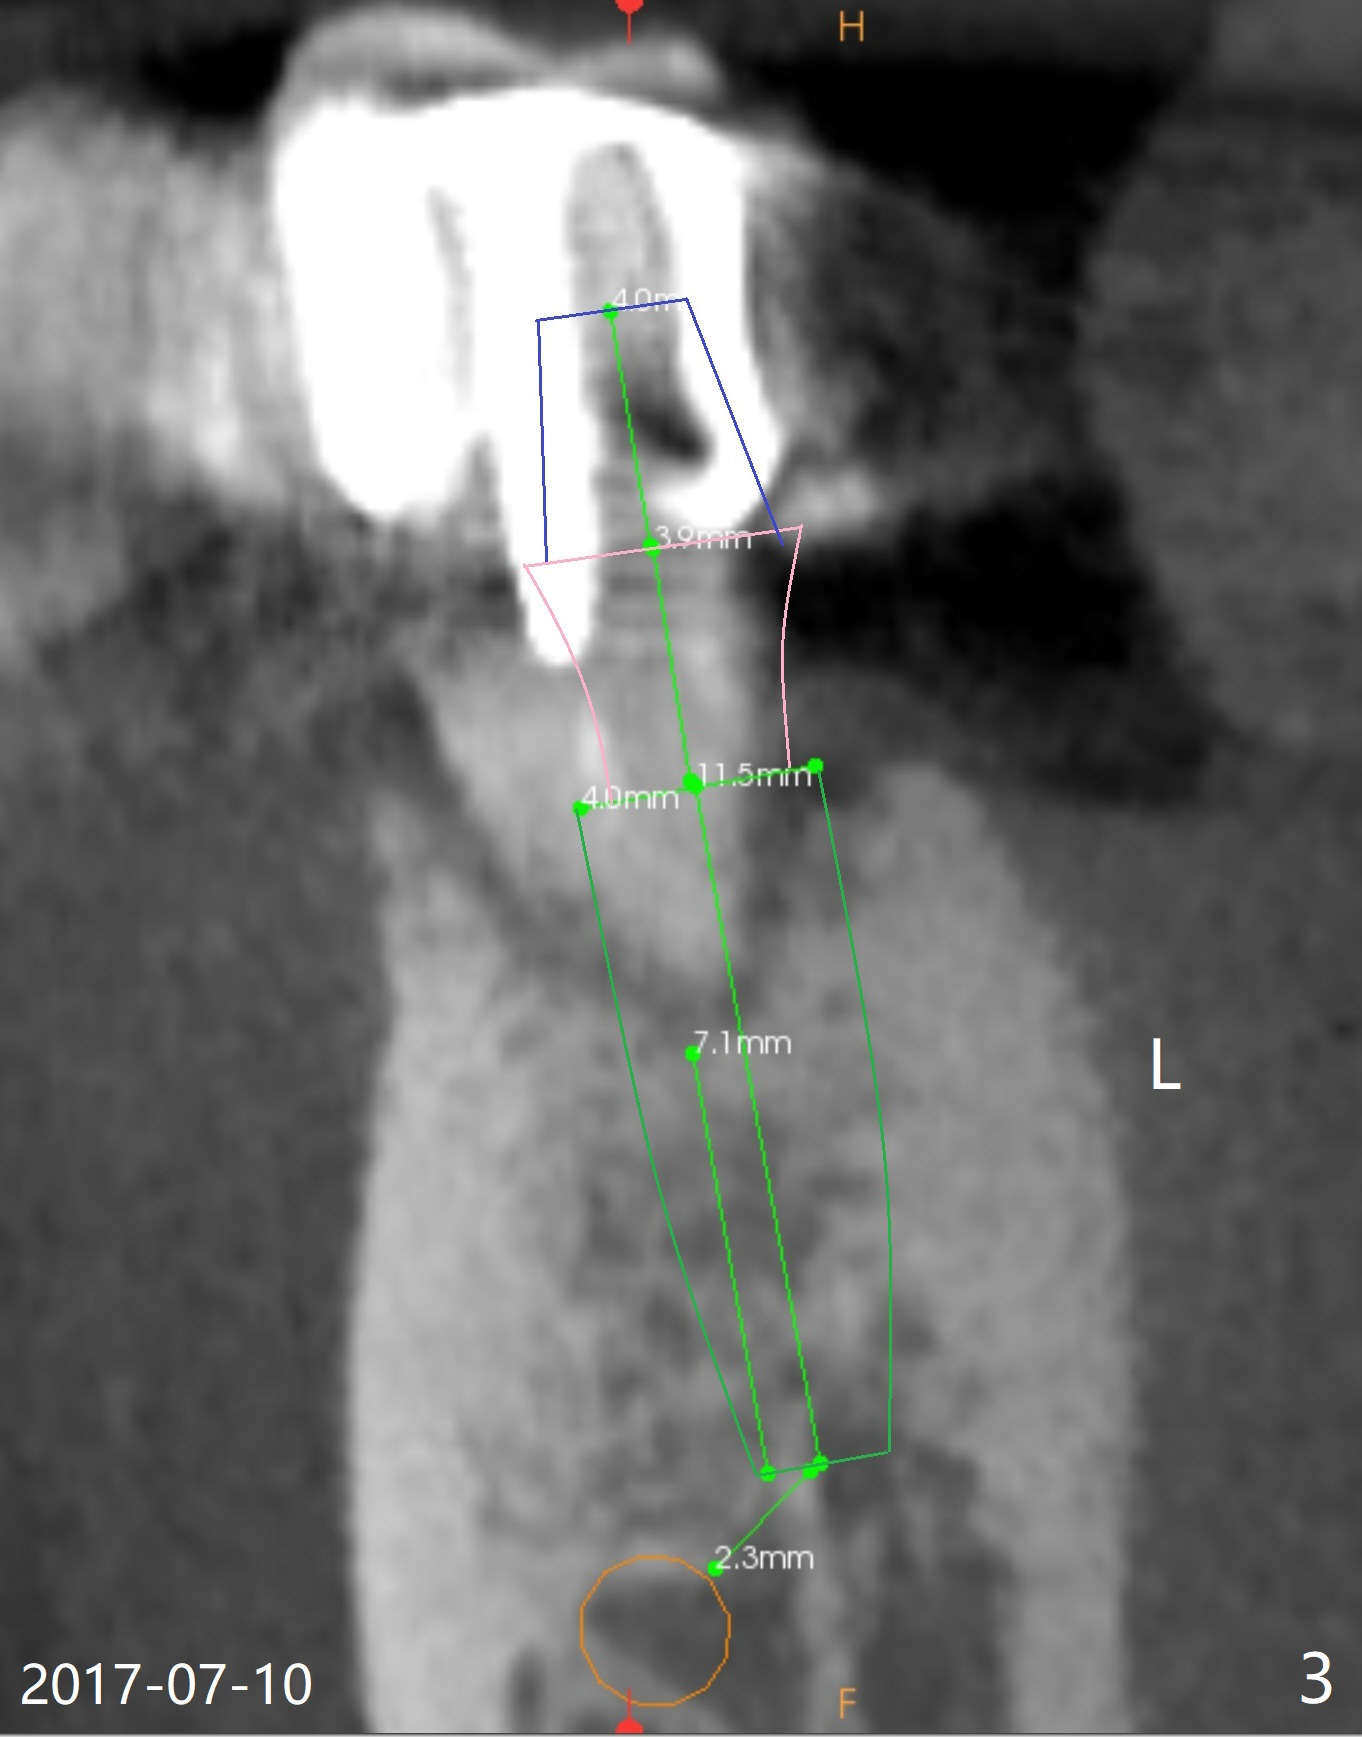

A 47-year-old man cannot chew in the lower right quadrant due to mobility of the tooth #29, which has a post (Fig.1 <). It appears that there is a buccal vertical fracture line. After extraction, osteotomy will be initiated in the mesiolingual aspect of the socket for 7 mm (Fig.2,3). The bone is dense (600-1,000 units); drills are required. Take a PA to confirm the trajectory. Following sequential osteotomy, place a 4x11mm dummy implant before placing a 4x9 or 11 mm definitive one, depending on bone resorption in the last 6 months (compare Fig.2,3 vs. 1).